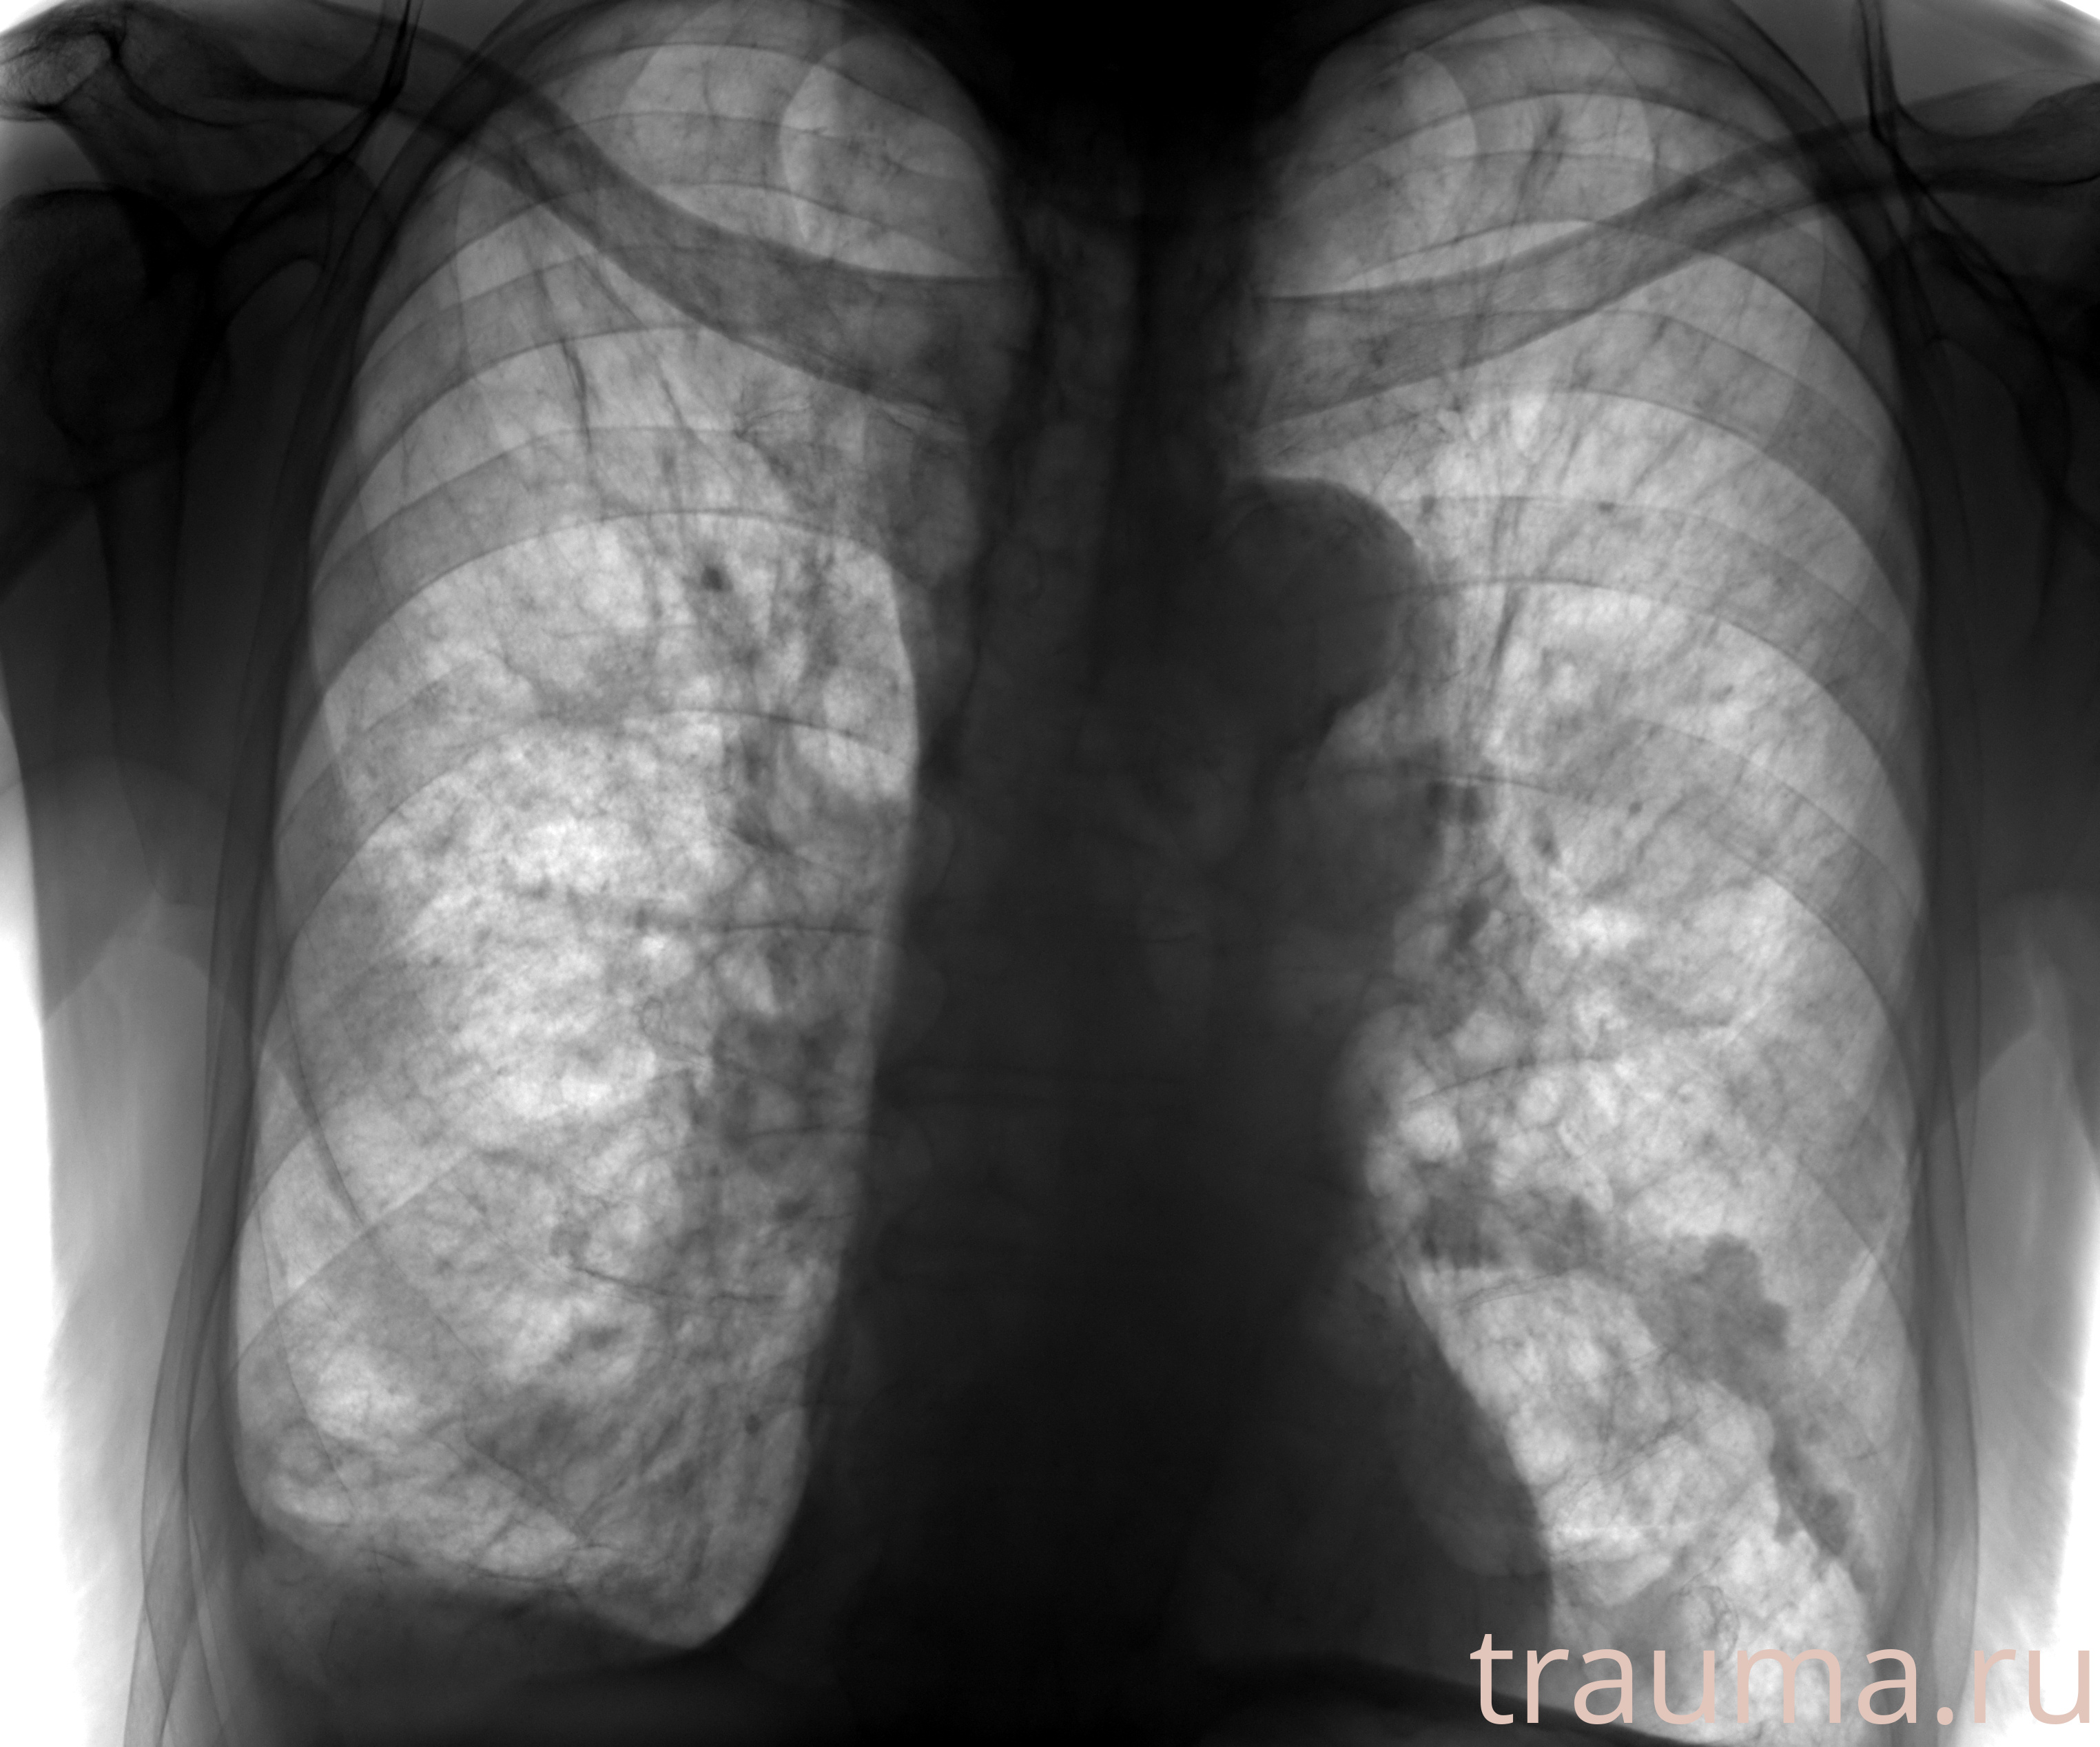

Рентгенограммы

Рентген на дому: по вашему адресу приезжает врач-рентгенолог, травматолог-ортопед с мобильным рентгеновским аппаратом, проводит диагностику травмы или заболевания, делает необходимые рентгенограммы, дает рекомендации по дальнейшему лечению. Получить качественные снимки в домашних условиях возможно благодаря уникальной методике, разработанной МосРентген Центром для института  Склифосовского